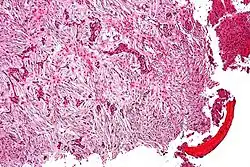

Coupe histologique d'une adamantinome.

Elle se caractérise par la présence de cellules épithéliales malignes dans un stroma fibreux ou ostéofibreux[4].